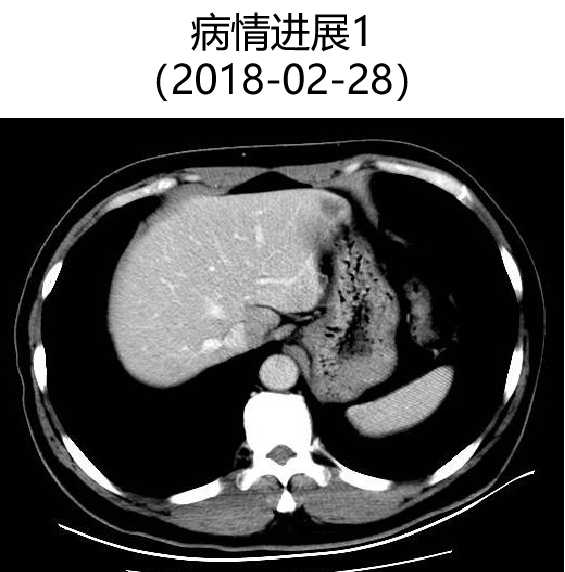

二 病例分享 专家简介 01 基本情况 患者:汪XX,男,63岁。身高 165cm;体重 65kg;体表面积 1.70m2;ECOG 1分。 主诉:反复解黏液血便3天。 对磁共振造影剂过敏,无食物、其他药物过敏史。既往史、个人史、婚育史、家族史均无特殊,无吸烟、饮酒史。 02 初诊病史 现病史:患者2017年3月初无明显诱因下解黏液血便,量中等,为鲜血,反复发作,无恶心、呕血、黑便、腹痛、腹泻、里急后重等不适。遂于2017年3月初就诊我院。 胸、腹、盆腔CT平扫+增强:乙状结肠肠壁明显增厚,肠腔狭窄,增强期强化明显;肝脏多发低密度病灶,增强期不规则强化,考虑乙状结肠癌伴肝脏多发转移。 03 治疗方案 【一线治疗】 2017-06-22 西妥昔单抗+FOLFIRI* Q2W×3 西妥昔单抗 900mg ivgtt D1; 5-氟尿嘧啶 0.6g iv D1,3.5g civ 48h; 亚叶酸钙 0.6g ivgtt D1; 伊立替康 280mg ivgtt D1。 第1疗程结束后黏液血便较前消失,过程顺利,耐受良好,无皮疹、腹泻等不良反应,治疗10疗程,疾病进展。 疗效评估-影像学(部分缓解,PR)。 2017-07-15 乙状结肠癌切除术* 手术记录:肿瘤位于乙状结肠,大小约4cm×3cm,未突破浆膜层,病灶周围可及数个稍肿大淋巴结,未及盆底种植结节。 手术过程顺利,术后恢复良好。 术后病理:(乙状结肠)中分化腺癌,浸润肠壁浆膜下层,两切缘阴性,未见脉管癌栓及神经束侵犯,LN 2/18(+) 2017-08-20 肝转移瘤切除术* 手术记录:肝脏肿瘤位于肝右叶,大小分别约2cm×1.5cm,1cm×1.2cm,其余肝表面未见异常结节,腹腔无腹水、无粘连。 手术过程顺利,术后恢复良好。 术后病理:(肝右叶病灶)中分化腺癌,结合临床病史,符合乙状结肠癌肝转移,肝组织切缘未见癌。 疗效评估-影像学(NED)。 2017-11-06 西妥昔单抗+FOLFIRI* Q2W×3 西妥昔单抗 900mg ivgtt D1; 5-氟尿嘧啶 0.6g iv D1,3.5g civ 48h; 亚叶酸钙 0.6g ivgtt D1; 伊立替康 280mg ivgtt D1; 过程顺利,无皮疹、腹泻等不良反应。每疗程后均予PEG-CSF预防性升白,耐受良好。 疗效评估-影像学(病情进展,PD1)。 胸、腹、盆腔CT平扫+增强:肝左外叶低密度灶,增强期不规则强化,结合病史,考虑结肠癌肝转移,余未见明显异常。 【二线治疗】 2018-03-06 肝左外叶肿瘤切除术* 术中探查见:肿瘤位于肝左外叶,质硬,边界不清,余肝脏表面未见异常结节灶,腹盆腔无腹水。 手术过程顺利,术后恢复良好。 术后病理示:(肝左叶)中分化腺癌,结合临床病史,符合结肠腺癌肝转移。 2018-04至2018-07 卡培他滨+奥沙利铂* Q3W×5 卡培他滨 1.5g BID D1-14; 奥沙利铂 200mg ivgtt D1。 过程顺利、耐受良好,无腹泻、神经毒性等不良反应。 疗效评估-影像学(病情进展,PD2)。 胸、腹、盆腔CT平扫+增强:肝尾状叶结节状异常密度灶,增强期不规则强化,结合病史,考虑结肠癌肝转移,余未见明显异常。 2018-07至2020-04 贝伐珠单抗+卡培他滨* Q3W×21 贝伐珠单抗 500mg ivgtt D1; 卡培他滨 1.5g BID D1-14。 过程顺利、耐受良好,期间曾出现II度腹泻,对症治疗后可恢复正常。无血压升高、出血、蛋白尿、手足皮肤反应。 疗效评估-影像学(最佳疗效,PR)。 疗效评估-影像学(病情进展,PD3)。 腹腔镜肝尾状叶切除术+腹腔粘连松解术* 术中探查见:肿瘤位于肝尾状叶,质硬,边界不清,余肝脏表面未见异常结节灶,腹盆腔无腹水。 手术过程顺利,术后恢复良好。 术后病理示:(肝尾状叶)中分化腺癌,结合临床病史,符合结肠腺癌肝转移。 2020-06至2021-09 贝伐珠单抗+卡培他滨* Q3W×16 贝伐珠单抗 500mg ivgtt D1; 卡培他滨 1.5g BID D1-14。 过程顺利、耐受良好,期间曾出现II度腹泻,对症治疗后可恢复正常。无血压升高、出血、蛋白尿、手足皮肤反应。 疗效评估-影像学(NED)。 疗效评估-影像学(NED)。 【三线治疗】 2021-12-16 西妥昔单抗+TAS-102* Q3-4W×2 西妥昔单抗 900mg ivgtt D1; TAS-102 60mg BID D1-5,8-12。 过程顺利、耐受稍差,期间出现II度骨髓抑制(三系减少),对症治疗后可恢复正常。无皮疹、输液反应等。 疗效评估-影像学(部分缓解,PR)。 04 治疗小结